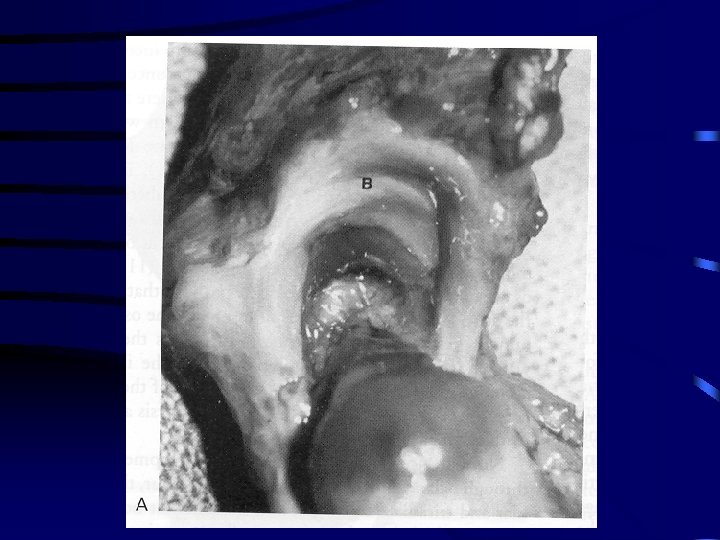

DDH • Tight fit between head and acetabulum is absent and head can glide in and out of acetabulum • hypertrophied ridge of acetabular cartilage in superior, posterior and inferior aspects of acetabulum called “ neolimbus” • often a trough or grove in this cartilage due to pressure from femoral head or neck • 98% DDH that occur around or at birth have these changes and are reversible in the newborn • 2% newborns with teratologic or antenatal dislocations and no syndrome have these changes

Obstacles to Reduction • Extra- articular – Iliopsoas tendon – adductors • Intra-articular – inverted hypertrophic labrum – tranverse acetabular ligament – pulvinar, ligamentum teres – constricted anteromedial capsule espec in late cases • neolimbus is not an obstacle to reduction and represents epiphyseal cartilage that must not be removed as this impairs acetabular development